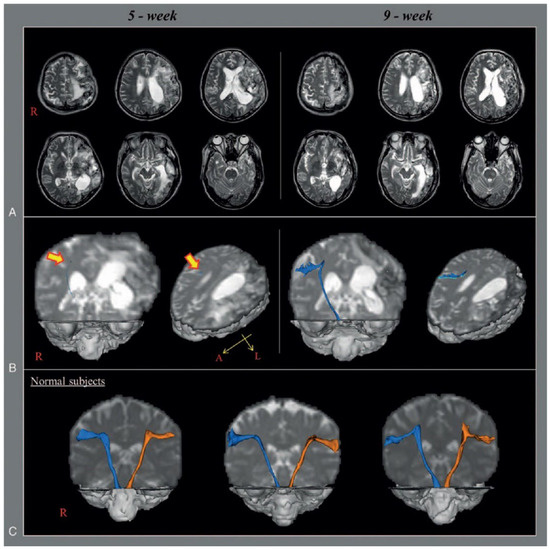

Jang et al. (2020) studied stroke patients (experimental group, n = 7, lateral medullary syndrome due to dorsolateral medullary infarction) and normal individuals (control group, n = 10) using DTT to compare parameters according to medial and lateral vestibulospinal tract damage and to determine the association of central vestibular disorder with dysphagia [38] (Figure 4). The experimental group presented with typical central vestibular disorders (dysphagia: n = 6, vertigo: n = 6, ataxia: n = 4, dysarthria: n = 3). DTT was performed at an average of 2 weeks after onset, and FA, MD, and TV of the corticospinal tracts (CST) were measured together for comparative analysis of medial and lateral VST and motor function and compared with DTT results of 10 control subjects. The results showed that in the CST and medial VST, the FA, MD, and TV in both sides were not significantly different from the control group, but in the lateral VST, FA values in the non-affected side were significantly reduced compared to the control group, and both FA and TV values in the affected side were significantly reduced compared to the control group. These findings suggest that metric analysis of lateral VST using DTT can help assess central vestibular sign symptoms such as dysphagia in patients with lateral medullary syndrome and in planning future interventions. Some limitations of this study are as follows: the small number of subjects in the study; the small size of the vestibular nuclei, which prevented the researchers from precisely positioning the ROI; the lack of data on long-term follow-up; the researchers may have underestimated or overestimated the fiber tracts of the VST; and the researchers could not reconstruct the full length of the lateral VST.

Figure 4.

Anatomical structure of VST captured using DTT [38]. (A) Brain MR images at 2 weeks after onset show an infarction in the right dorsolateral medulla. (B) Results of diffusion tensor tractography (DTT). DTTs for both the medial vestibulospinal tract (VST) and the left lateral VST originate from the pontine vestibular nuclei and terminate at upper cervical cord. By contrast, DTT for the right lateral VST is not reconstructed between the lateral vestibular nuclei in pons and the upper cervical cord. Copyright by Jang et al. (2020) [38].